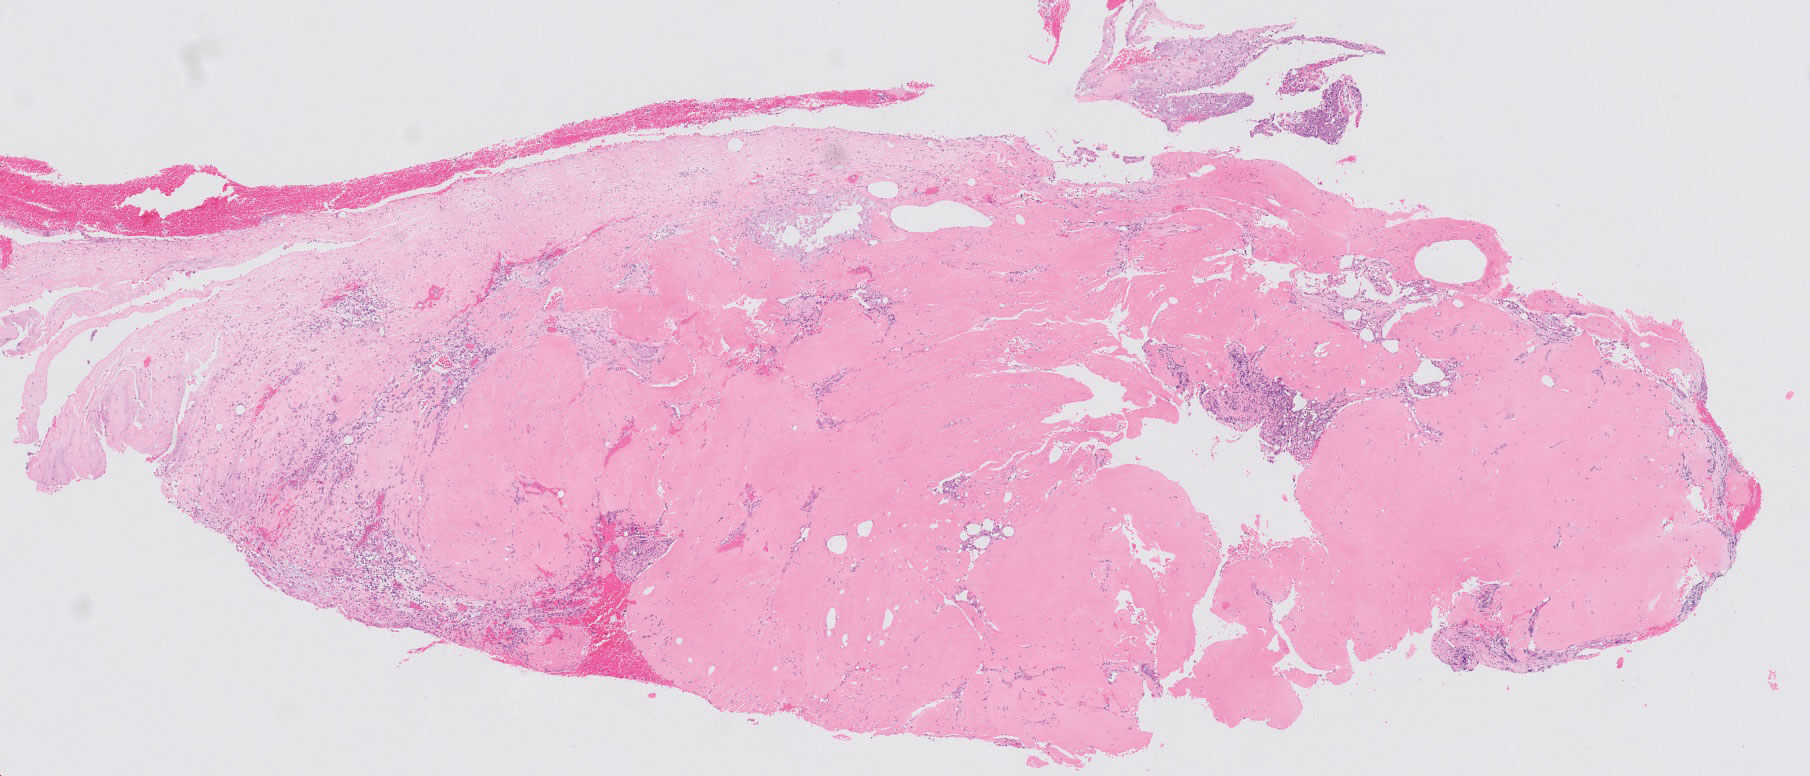

Figure 2: H+E 2x.

Figures 2 and 3 show representative H+E-stained sections of the lesion. Special stain Congo red was also done but this was negative (not shown).

- Figures 1 and 2 demonstrate ulcerated conjunctiva with active chronic inflammation, granulation tissue and thick and fibrinous dense eosinophilic amorphous hyalinised material. The eosinophilic deposits were negative for Congo red stain.